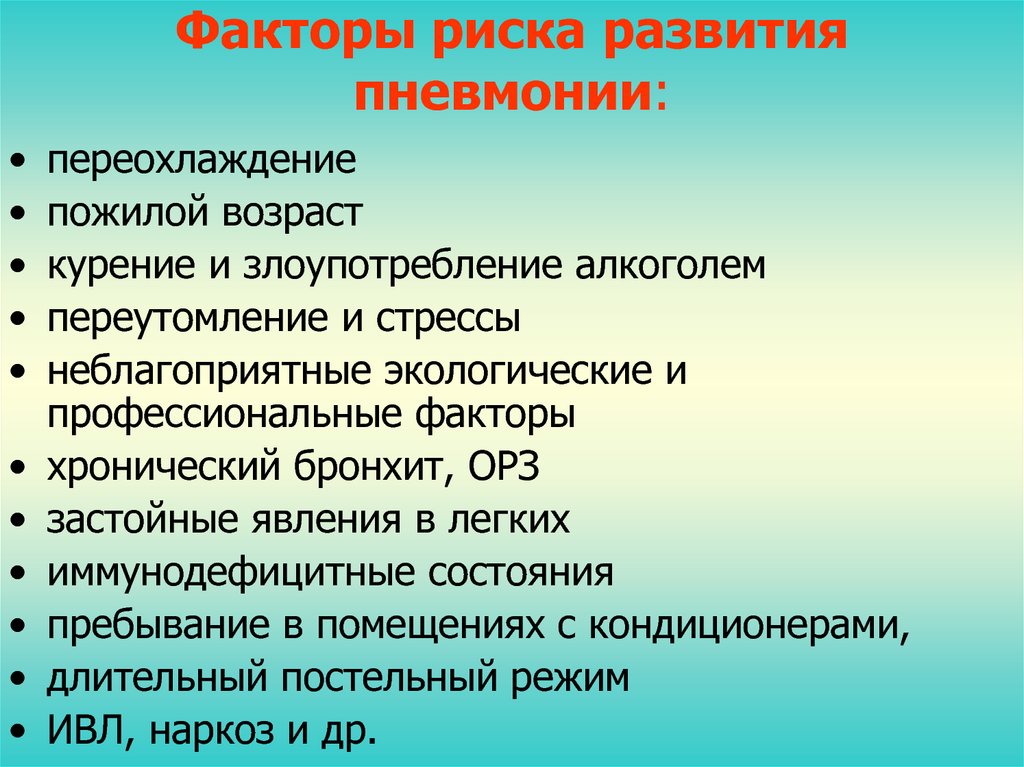

Группа риска

Вероятность возникновения пневмонии повышается при переохлаждении, респираторных заболеваниях, стрессе, переутомлении.

В группу риска входят маленькие дети (до 5 лет), пожилые люди (старше 65 лет), лица с ослабленной иммунной системой (например, больные сахарным диабетом, СПИДом, онкологическими заболеваниями и др. ), с врожденными пороками бронхо-легочной системы, имеющие хронические заболевания (болезни сердца, пиелонефрит и др.), астматики, лежачие больные, а также курящие и злоупотребляющие спиртным.